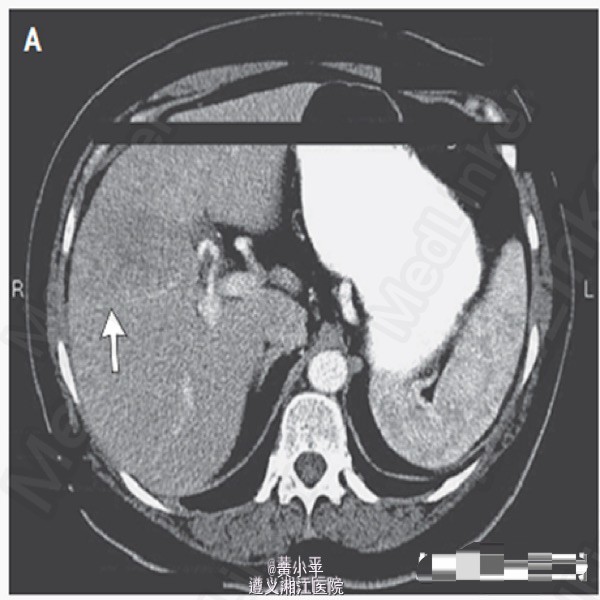

查体:BP190/97mmHg,其余生命体征正常。腹软,于右上腹可触及柔软肝脏边缘,未及肝脾肿大或腹胀。余查体正常。肝脏MRI增强发现右叶9.4cm×12.3cm×8.5cm异质性增强肿块。另有一处在第七段发现5mm病变,考虑可能为转移灶;余肝右叶多发小病灶考虑为血管瘤。(图1-3) 血浆皮质醇水平为23.5μg/dL(648 nmol/L)(参考值5-15μg/dL);血管活性肠多肽32pg /mL(参考值小于75)。入院第二天行SPECT,提示肝右叶大范围喷曲肽再摄取降低,符合MRI所示。